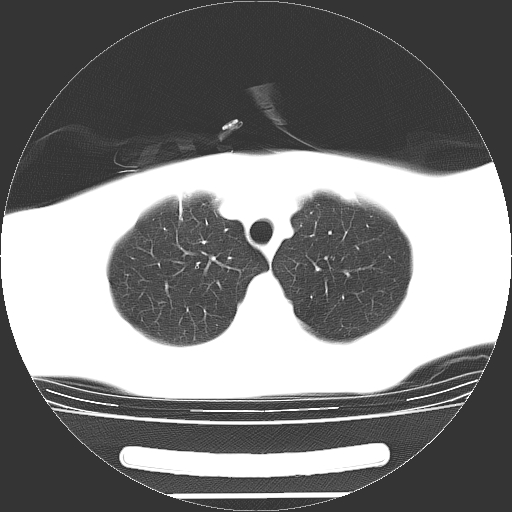

标题: CT19767:男,20岁,右侧气胸行闭式引流术后五天CT检查。 [打印本页]

男,20岁,右侧气胸行闭式引流术后五天ct检查看肺内是否有肺大泡,纵隔窗未见异常,未上传。

1)右侧胸腔闭式引流术后导管留置。2)右肺未见肺大泡。

未见肺大泡,还有微量气体。